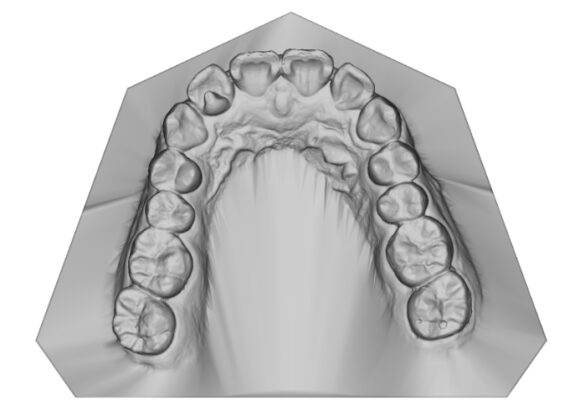

El escaneo dental es un dispositivo digital utilizado para capturar impresiones tridimensionales de la boca del paciente.

Este tipo de escaneo permite recrear la dentadura con una precisión que supera con mucho las muestras tomadas con materiales de impresión tradicionales.

• Réplica exacta de las estructuras dentales y tejidos adyacentes del paciente.

• La ventaja es que su consulta se actualiza dejando atrás modelos de yeso que se rompen o maltratan y que además debe de almacenar. Le damos la alternativa de almacenarlos digitalmente teniéndolos virtualmente en su computadora y si requiere imprimirlos podemos realizarlo en el momento que necesite.

• Los escaneos son considerados tan precisos si no más exacto que los moldes de yeso. El proceso de escaneo es más cómodo para pacientes especialmente con reflejo nauseoso.